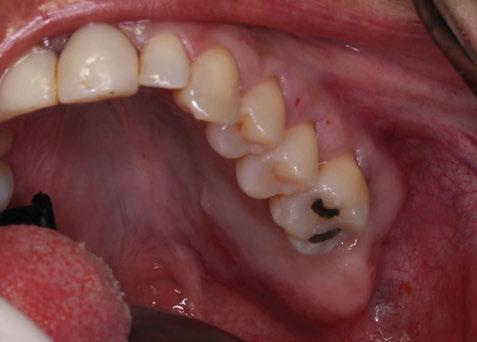

Para ilustrar el proceso, presentamos el caso de una mujer joven diagnosticada de carcinoma adenoide quístico en la región posterior del hemipaladar izquierdo (Figuras 1 y 2). El procedimiento quirúrgico realizado fue una

Figura 1. Imagen preoperatoria de la paciente.

Figura 2. Carcinoma adenoide quístico en región posterior del hemimaxilar izquierdo.